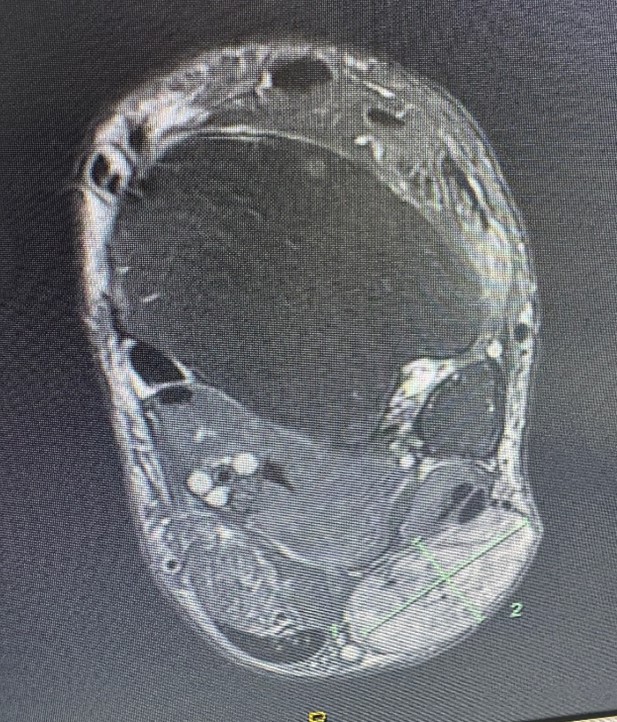

67 year old man with a large slowly growing tumour on the back of his ankle. MRI showed central necrosis and the size was of concern. The tumour turned out to be a benign angioleiomyoma